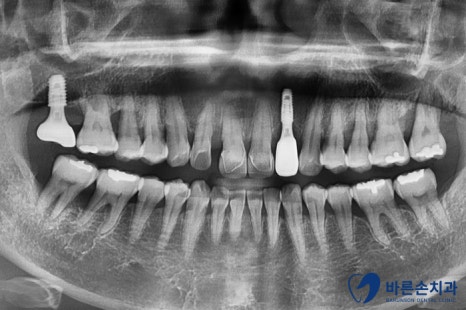

보시면 앞니 하나가 유독 뼈가 내려가 있는 걸 볼 수 있어요.

치아를 잡아주는 뼈가 별로 없다보니

치아가 밑으로 내려오면서 많이 흔들리는 상태였습니다.ㅠㅠ

그래서 발치 후 임플란트로 치료계획을 세웁니다!

이미 상실되어 있는 어금니와 함께 앞니 임플란트를 가지런히 심었습니다.